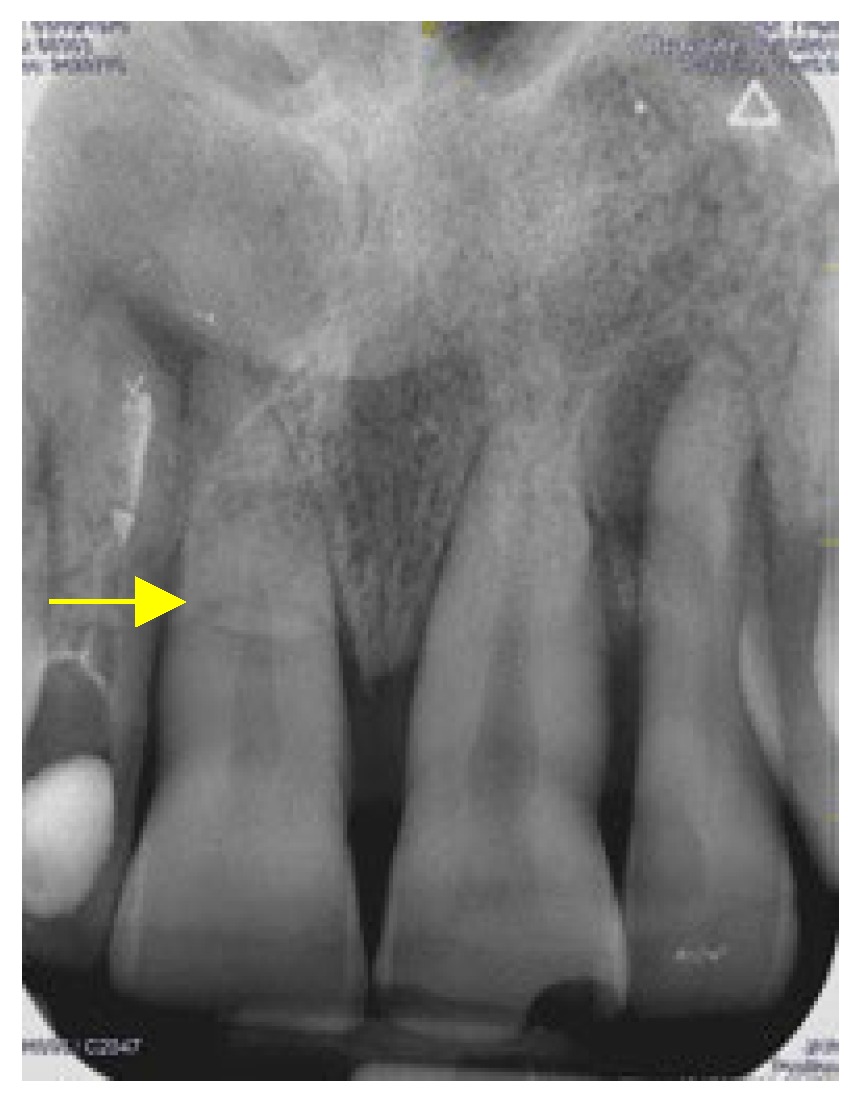

3.1. Horizontal Fractures

- A. No pulp involvement (Figure 5)

3.2. Treatment